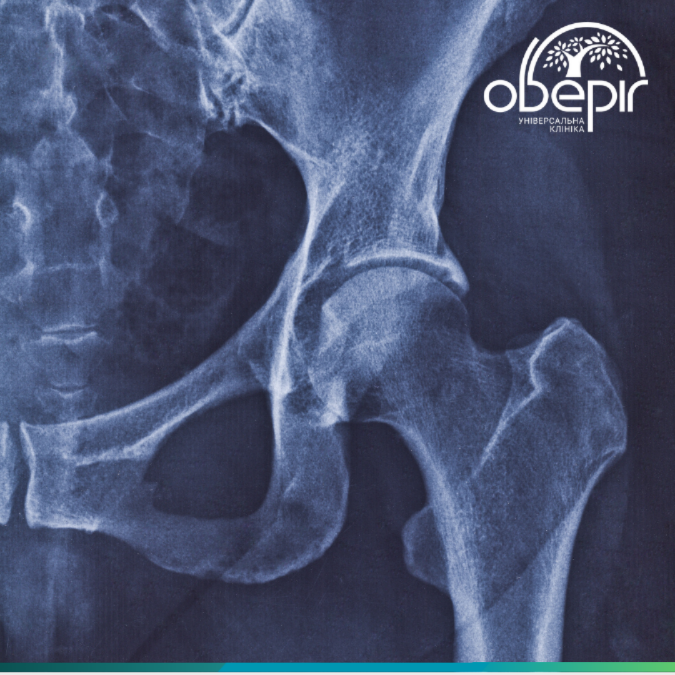

Coxarthrosis: When the thigh "creaks" and hurts